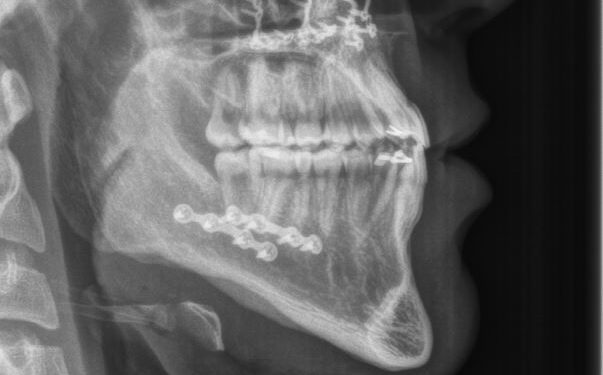

Jaw Surgery